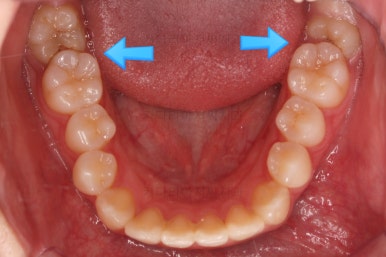

맨 안쪽 치아가 마치 사랑니인 것처럼 누워있고 애매하게 나와있었어요.

문제는 해당 치아가 썩었다는건데 기울어 있는 치아를 제대로 치료할 방법은 사실상 없죠. 앞에 치아에 가려진 부분이 썩었으니깐요.

저대로 계속 놔두게 되면 누워있는 어금니 + 앞쪽 어금니 두 개가 다 상해서 결국 뽑아야 되는 상황까지 벌어질 수 있어요. 그것도 양쪽으로 모두 다 요.

치료 방법 1. : 누워있는 치아(+사랑니)를 뽑고 임플란트를 한다.(혹은 그냥 내버려둔다.)

치료방법 2. : 사랑니를 뽑고 누워있는 치아를 바로 세운 뒤(교정치료) 충치치료를 해서 오래 오래 사용한다.

하지만 이번 환자분의 경우 기울어진 치아에 사랑니가 어부바 하듯이 올라탄 형태라 어금니를 다역오는 방법도 적절하지 않은 상황이었어요.

결국 치아교정을 통해 위치를 바로 잡아주기로 했습니다.

쓰러져 있던 치아도 장치를 부착하여 일으켜 세워주는 힘을 줍니다.

자칫 나머지 치열이 틀어질 수 있기 때문에 아랫니에는 부산교정 미니스크류를 이용해서 반작용을 막아줍니다.

점점 뒤쪽 치아가 바로 일으켜세워지고 있네요.